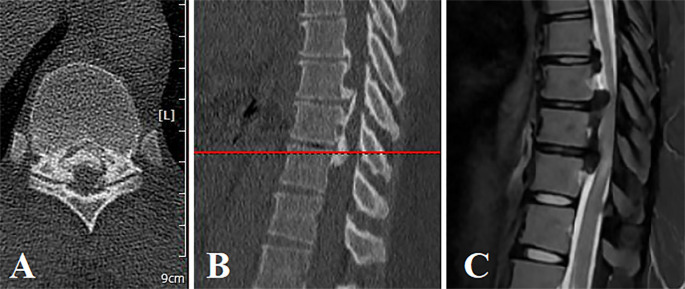

Thoracic ossification of the posterior longitudinal ligament (OPLL) is a rare condition that is mainly accompanied by cervical OPLL or ossification of thoracic ligamentum flavum. In case of causing neurological manifestations, it is preferred to treat the condition surgically. Several surgical procedures were introduced, including anterior, posterior, or combined approaches. Laminectomy with instrumented fusion is the most popular procedure utilized via the posterior approach. A 32-year-old obese woman, who suffered from back pain and weakness in both lower extremities for one month, was referred to our spine outpatient clinic. Imaging revealed lower thoracic OPLL (T7/T8 & T8/T9 & T9/T10). The posterior longitudinal ligament had a mixed ossification pattern (beaked and continuing cylindrical). To maintain thoracic spine stability and prevent future kyphosis, we performed laminectomy and long segment fixation (T7 to T12). The post-operative neurological examination revealed a considerable increase in muscle strength and significant pain relief.